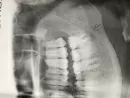

Действительно, по снимку у верхушки медиального корня зуба мудрости есть воспалительный процесс (апикальный периодонтит) из-за его обострения у Вас возникли подобные жалобы.

Снять острую фазу помогут антибиотики и противовоспалительные средства. Улучшение самочувствия должно наступить через 5-7 дней после начала приема, но после периодонтит вылечить необходимо (эндодонтическое перелечивание зуба).